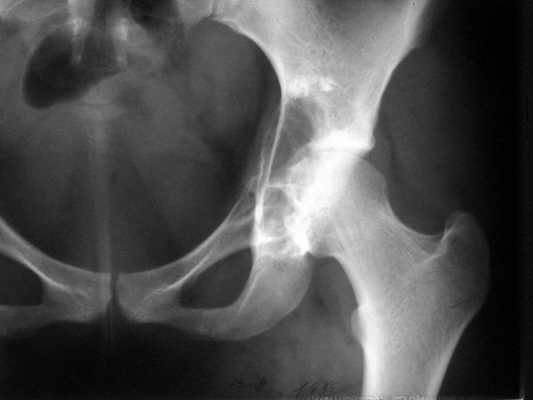

A female 22 years old admitted with the hip protrusion. Xrays are 12 months apart. Biopsy doesn't confirm malignization. What surgery can be done here? Is there any chance of primary hip replacement?

I think you need to get the opinion of a musculoskeletal oncologist, but it appears that this patient has an aggressive giant cell tumor and will likely require an aggressive wide excision. As a result reconstruction will be difficult.